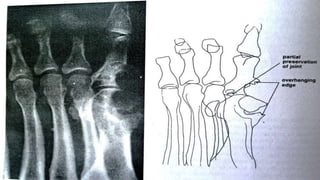

RADIOGRAPHIC EXAMINATION

• Juxta-articular bony erosion associated with

periarticular tophi

• Subchondral erosions with overhanging bony

edges

RADIOGRAPHIC EXAMINATION To excludeother kinds of arthritis: • Tophi • Normal mineralization • Asymmetric polyarticular distribution • Juxta-articular bony erosion associated with periarticular tophi • Subchondral erosions with overhanging bony edges